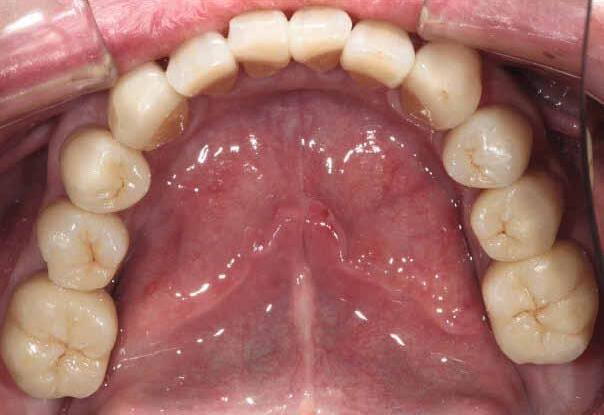

This case was performed by Dr Homa Zadeh, DDS, PhD, a respected leader in periodontology and implant dentistry. Dr Zadeh’s approach emphasizes biologically driven protocols and evidence-based techniques, making this case a strong example of clinical excellence using the Tapered Pro Conical system. It involves the replacement of two front anterior teeth after they fractured off and the full restoration process.

Fig 1. Patient anterior situation. Two anterior crowns fractured off.

Fig 2. Intraoral radiograph indicating tooth structural loss extent.

Fig 3. Provisional restorations on central incisors and gingival images. The gingival contours were optimal, and the gingival phenotype was thick.

Fig 4. Alveolar bone imaging. The alveolar bone was intact, and the alveolar crest was approximately 4mm apical to the restorative margin.

Fig 5. Central incisors extracted using minimally invasive protocol. Alveolar bone and gingival tissues were intact after extraction

Fig 6. BioHorizons Tapered Pro Conical implants of 3.8 x 15mm placed according to the plan.

Fig 7. Implants immediately after installation.

Fig 8. Scanbody installation for custom abutment and definite restoration fabrication.

Fig 9. Periapical radiograph for verification of proper seating of the scanbodies.

Fig 11. Bone graft filling the horizontal gap between socket and implants.

Fig 12. Screw-retained provisional restoration placed into implants, with LPRF placed to protect graft material.

Fig 13. Radiograph of implants, grafts and Provisionals.

Fig 14. Clinical view at two days post-operative visit.

Fig 15. Clinical view at two days post-operative visit

Fig 16. Patient’s smile after implantation and previsualization